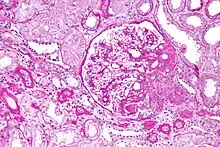

| Light micrograph of focal segmental glomerulosclerosis, hilar variant. Kidney biopsy. PAS stain. | |

On histology, FSGS manifests as scarring (sclerosis) to segments of glomeruli; moreover, only a portion of glomeruli are affected.[7][20][21] The focal and segmental nature of disease seen on histology help to distinguish FSGS from other types of glomerular sclerosis.[21]

Diagnosis of FSGS is made by renal biopsy that includes at least fifteen serial cuts with at least eight glomeruli.[31][32] Histologic features include sclerosis (scarring) of a portion (average: 15%) of the glomerular space, with only a portion of glomeruli manifesting any sclerosis.[32]